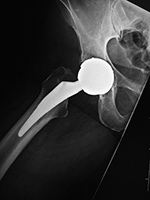

Partial Hip Replacement

There are three basic types of hip arthroplasty. Partial hip replacement or hip hemiarthroplasty replaces the femoral head and neck and leaves intact the native acetabulum. Hip hemiarthroplasty may consist of a single metallic unit, a unipolar hemiarthroplasty or endoprosthesis (figure: hip endoprosthesis). Or it may consist of a bipolar hip hemiarthroplasty in which there is replacement of the femoral head and neck and placement of a prosthetic acetabulum which is press fit into the native acetabulum. The bipolar hip prosthesis acetabulum is a polyethylene lined metal cup. It fits into a small femoral head which is locked to the attached metal femoral stem (Mulcahy, 2012). The bipolar hip hemiarthroplasty allows motion between the prosthetic femoral head and the polyethylene lined cup as well as between the cup and the native acetabulum (figure: bipolar hip prosthesis).

Approximately one-half of hip fractures occur in the femoral neck (intracapsular hip fracture). The unipolar hemiarthroplasty (endoprosthesis) is typically used in

elderly patients with lower life expectancy for

treatment of intracapsular hip fractures. There is removal of the femoral head and placement of a press-fit or cemented

femoral component with a head diameter that

matches that of the acetabulum and articulates

directly with the native acetabular articular cartilage. This is a less traumatic surgery for the patient and enables the patient to have reasonable ambulation quickly after surgery.

| Unipolar hip hemiarthroplasties (endoprostheses) |

Unipolar hip hemiarthroplasty (endoprosthesis) with a cemented femoral component |

Modular non-cemented unipolar hip hemiarthroplasty (endoprosthesis) |

| These are single piece prostheses press fit into the native acetabulum and the native femur. From Benjamin, 1994 |

Note the collar abutting the femoral calcar. From Benjamin, 1994 |

Note the collar abutting the femoral calcar. |